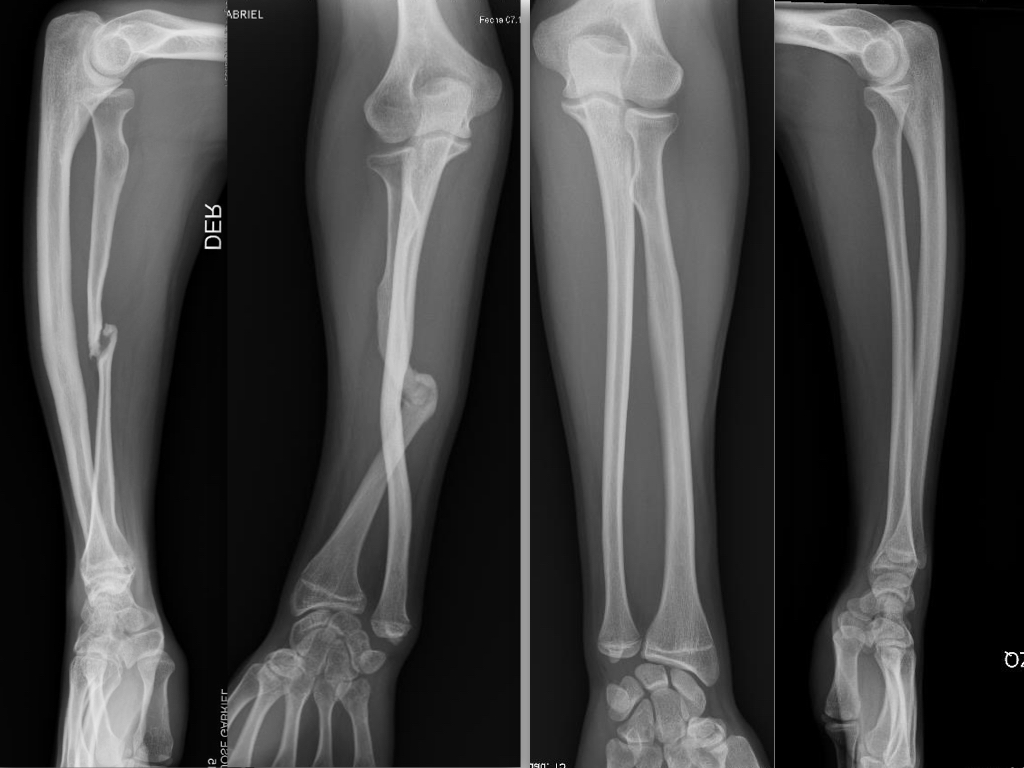

Experiencia inicial en un centro de alta complejidad con el injerto vascularizado de peroné en defectos óseos segmentarios del miembro superior. [Early experience in a high complexity Hospital with the vascularized fibular graft in segmental bone defects of the upper limb.]